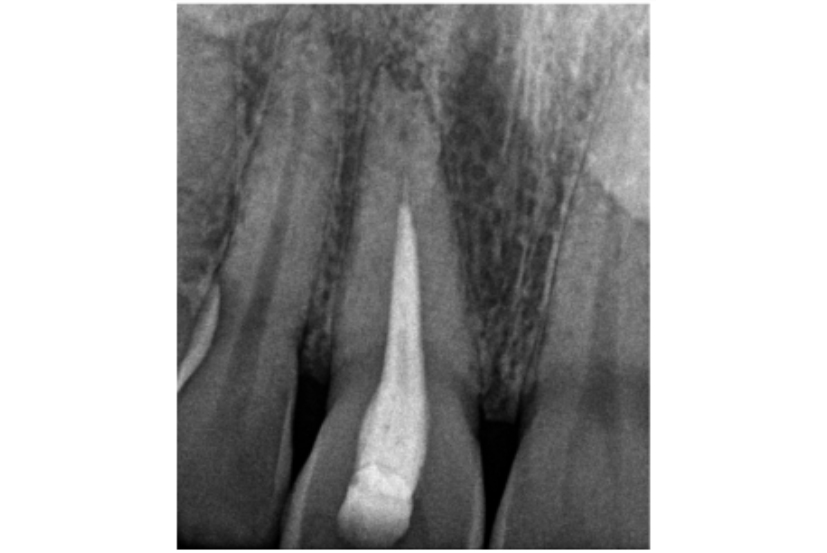

Figure 1: Pulp canal obliteration (PCO). The patient had trauma to UL1 15 years ago and developed a yellow discolouration over time. She was keen to improve the appearance of the tooth. The UL1 was asymptomatic and did not respond to sensibility testing.

Radiographically, UL1 had a normal PDL width and an intact lamina dura could be seen around the tooth. A diagnosis of pulp canal obliteration was reached for UL1. There was no endodontic infection and the patient was advised to have external tooth whitening; this will take longer and a veneer might be necessary if a satisfactory result can’t be achieved with external whitening alone. Figure 1a: Preoperative photograph. Figure 1b: Preoperative radiograph.